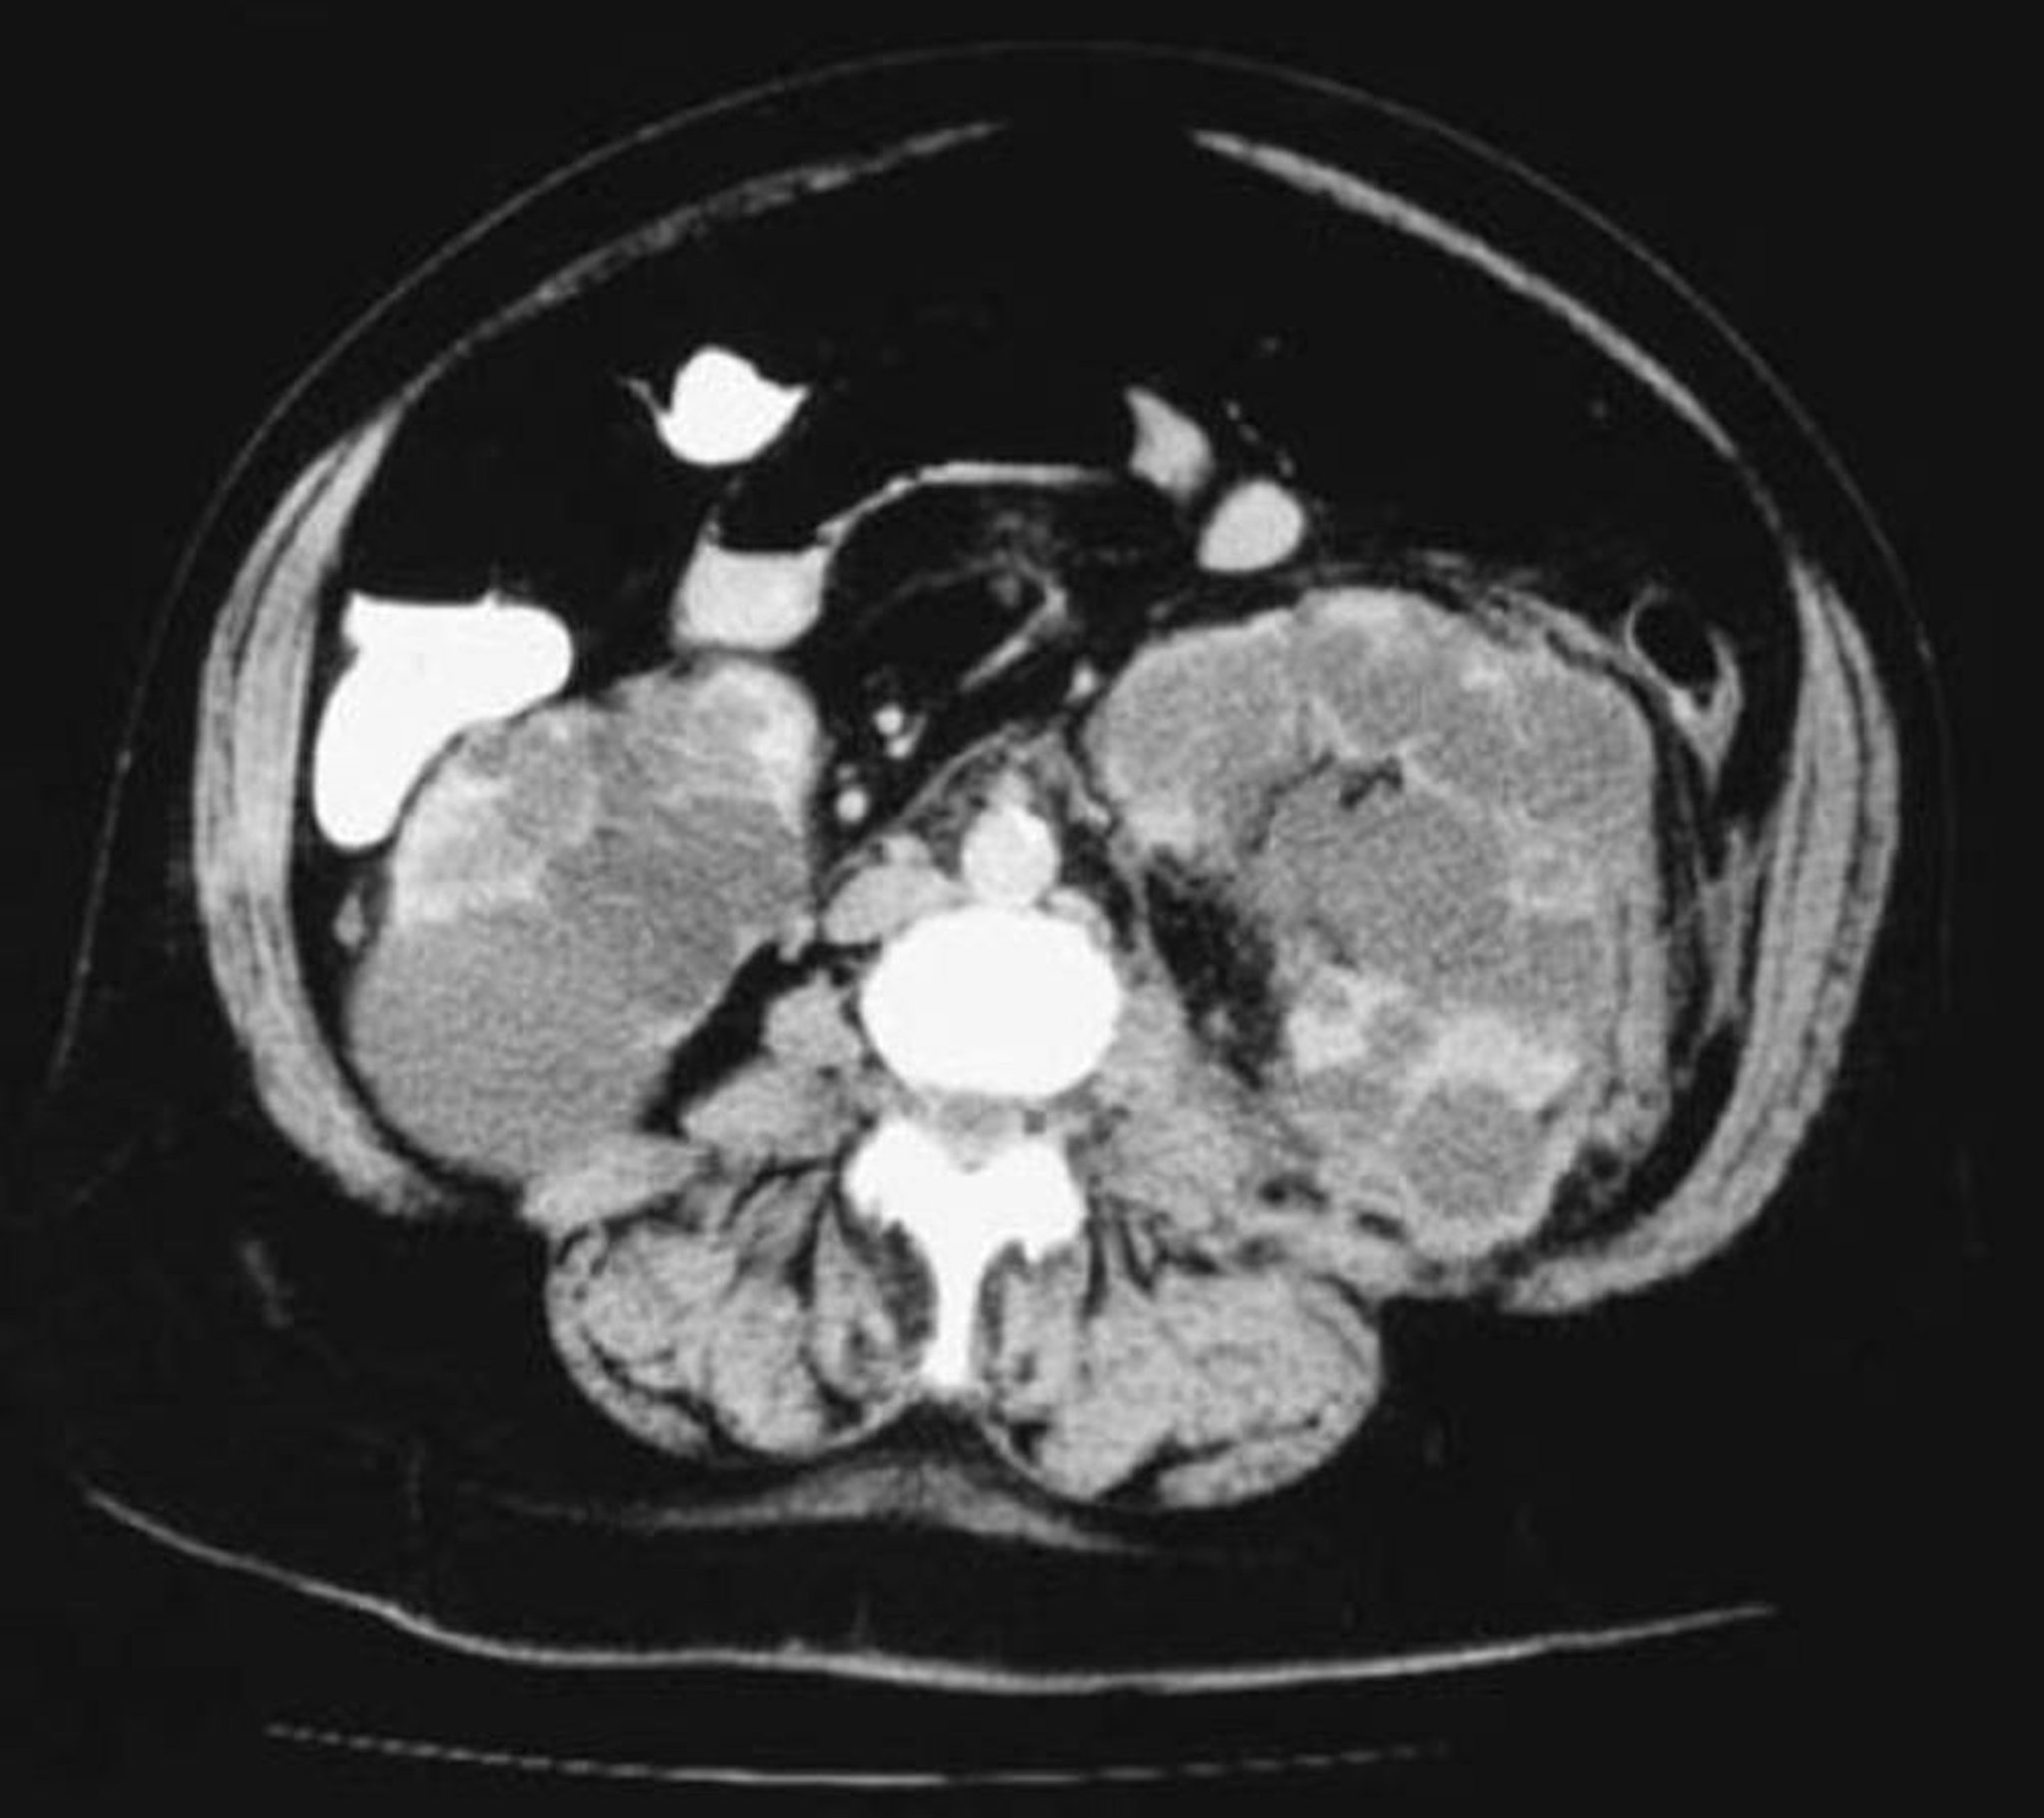

КТ полікістозних нирок (аксіальна проекція)

This CT scan of the kidneys shows numerous cysts varying in size. Little renal parenchyma is left.